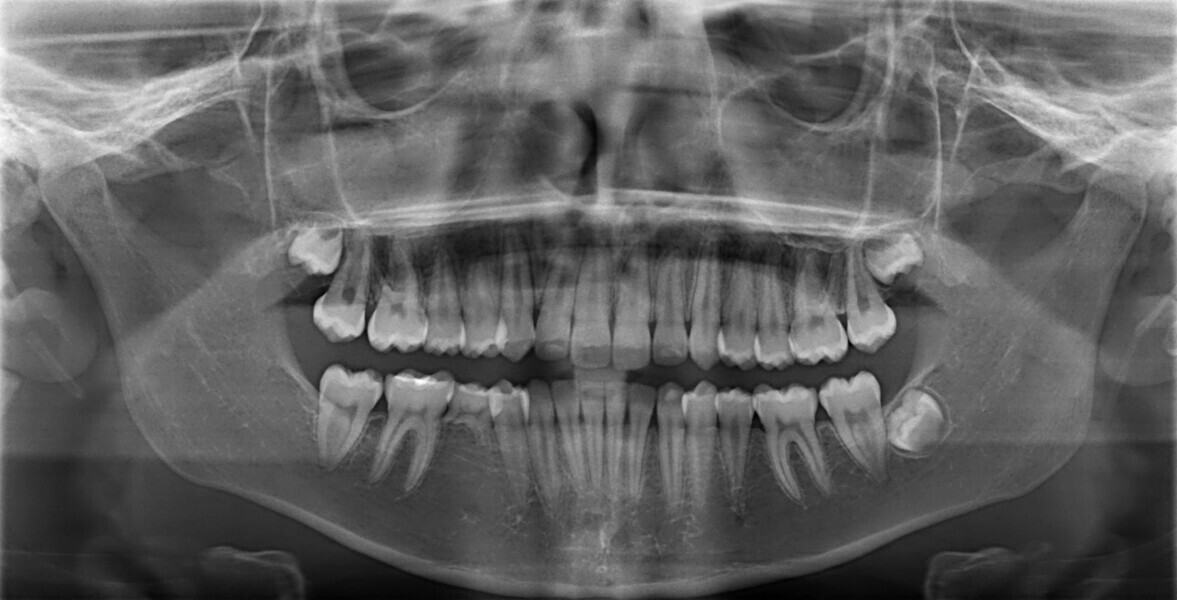

A 14-year-old female patient presented with the chief complaint of midline deviation and dental crowding in both arches. Facial analysis showed a hypodivergent growth pattern, a normal nasolabial angle, a harmonious profile and proper chin projection. Clinical examination revealed a Class III skeletal relationship (ANB = 0°) and Class I molar relationship. The maxillary right canine was absent, and this had led to space loss and mesial drift of posterior teeth on the right side, resulting in a slight Class II molar relationship. The maxillary left canine had erupted in a high position. The mandibular arch displayed crowding despite the agenesis of the right second premolar and the persistence of the primary molar (Figs. 3–11). The radiograph showed the probably premature loss of the maxillary right primary canine and consequently impacted maxillary right permanent canine, and the agenesis of the mandibular right second premolar and the mandibular right third molar (Fig. 12).

Cephalometric analysis showed normal incisor inclination (U1–PP = 112°) and slightly uprighted mandibular incisors (IMPA = 88°), consistent with dental compensation commonly observed in Class III skeletal malocclusions. Cephalometric analysis confirmed a reduced lower anterior facial height associated with a hypodivergent pattern (Figs. 13 & 14).